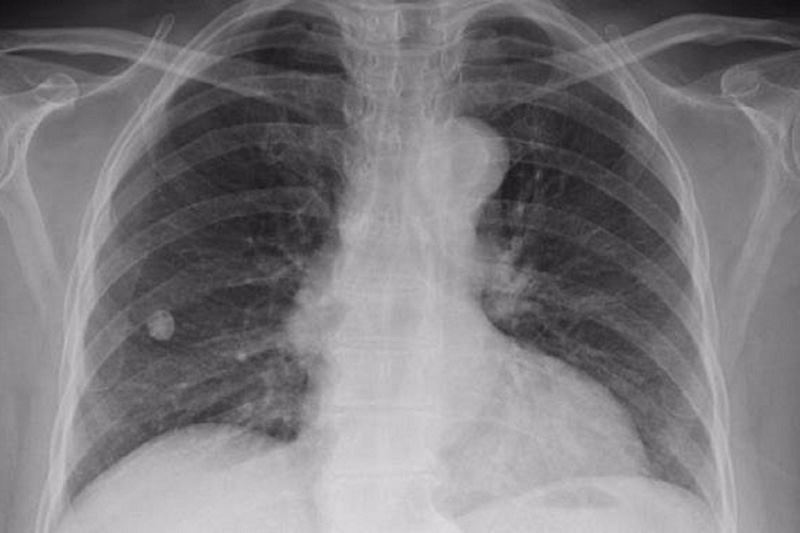

رئیس شبکه بهداشت زاهدان به مناسبت ۲۳مهر روزملی مبارزه با سل گفت: شیوع سل در سیستان و بلوچستان بالاتر از میانگین کشوری است.

او افزود: درحالی که میانگین متوسط ابتلا به سل در کشور به ازای هر ۱۰۰ هزار نفر جمعیت ۱۱نفر است اما این آمار در استان ۲۰ نفر در ۱۰۰ هزار نفر است.

رئیس شبکه بهداشت زاهدان اظهار کرد: آمار سیستان و بلوچستان در خصوص ابتلا به سل با توجه به وجود ریزگردها در بیشتر ایام سال بخصوص در شمال استان دو برابر آمار کشوری است.